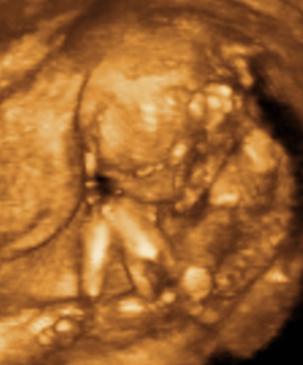

Ui.: Kedden megyünk genetikai UH-ra, szorítsatok nekem. Aztán majd jelentkezem.